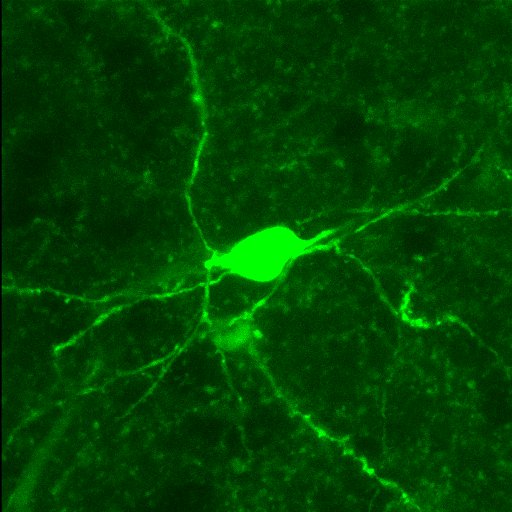

LeGates’s 2018 paper explored the details of a specific communication pathway between two brain regions: the hippocampus and the nucleus accumbens. She found that this particular synapse (a connection between the two) is pivotal to reward-seeking behavior in mice. This mechanism is highly conserved across species, including in humans.

“There’s this increasingly popular hypothesis in the field that the strength of synapses, like ones between the hippocampus and the nucleus accumbens, are really what underlies depression,” LeGates says. “In depression, you have a weakening of these synapses, and antidepressants currently on the market act indirectly to restore them. By identifying the specific synapse involved, it would allow for a more targeted approach to treating disorders like depression.”

For example, a stimulus such as the company of a fellow mouse may be rewarding in the moment. If the connection between the nucleus accumbens and the hippocampus is blocked during the interaction, however, the mouse won’t remember where it had that rewarding experience. On the other hand, if that brain connection is stimulated even without the presence of a physical reward, the mouse will prefer the location where the brain stimulation occurred.